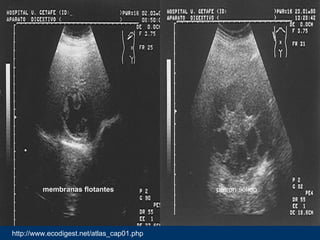

http://www.ecodigest.net/atlas_cap01.php

membranas flotantesmembranas flotantes patrón sólido

• #21 Imagen quística con membrana germinativa que está despegada y que tiene forma ondulada. Quiste hidatídico hepático tipo III(Clasificación de Gharbi) Imagen quística hepática de gran tamaño con múltiples vesículas hijas localizadas en la periferia y la matriz hidatídica que rellena el resto del quiste. Quiste hidatídico hepático tipo IV (Clasificación de Gharbi)